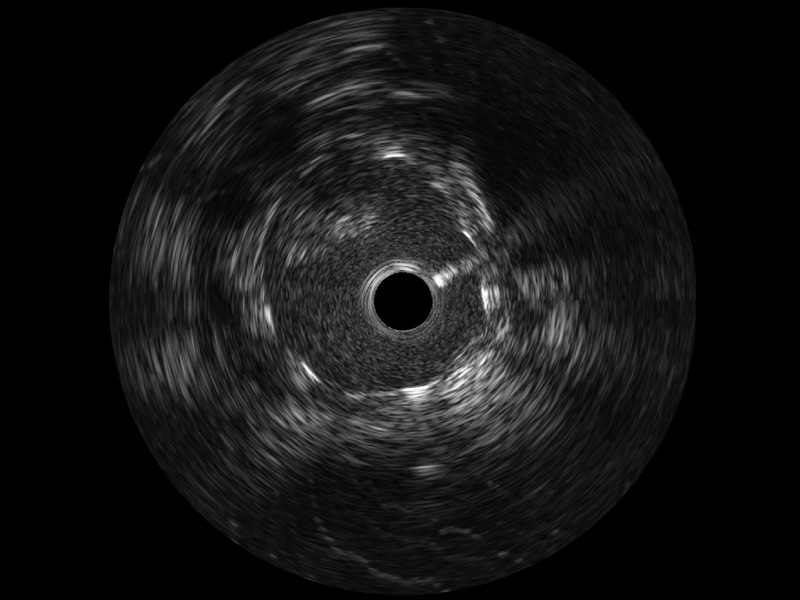

传统IVUS图像

对比传统IVUS导管成像,开立宽频IVUS图像的近场支架梁显影更细腻,远场中膜外血管仍清晰可辨,兼顾远中近,兼顾分辨力与穿透深度